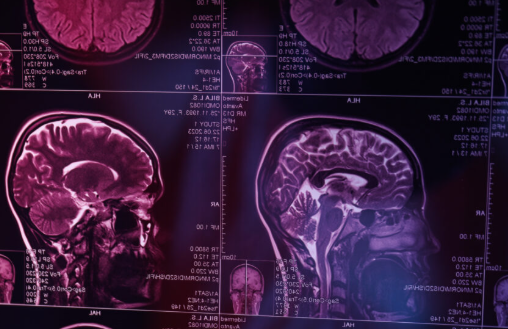

Kalp ve Damar Cerrahisi Uzmanı Doç. Dr. Macit Bitargil, "Şah damarı, boynun her iki yanında yer alan ve kalpten çıkıp direkt olarak beyine kan taşıyan ana damarlardır. Bu damarlarda zamanla kolesterol yüksekliği, tansiyon yüksekliği, sigara kullanımı, şeker hastalığı ve yaşlanma gibi nedenlerle plaklar oluşabilir" dedi. Doç. Dr. Bitargil, bu plakların damarı daraltarak beyne giden kan akış paternini bozduğunu kaydederek şunları söyledi: "Oluşan türbülan akım ve damardaki darlık sonucu sistem pıhtı üretebilir. Embolinin beyne ulaşması ve beyindeki ilgili merkezi etkilemesi sonucu geçici iskemik ataklar (TIA) veya kalıcı inme (felç) tablosu gelişebilir." İHTİMAL ÇOK YÜKSEK: Şah damarı hastalığının genellikle sessiz seyrettiğini aktaran Bitargil, ancak bazı öncü bulguların tehlikeyi önceden haber verebileceğini söyledi ve o belirtileri sıraladı: - Gözde saniyeler süren geçici kararma, görme kaybı, - Dudak kenarında uyuşma, asimetri oluşması